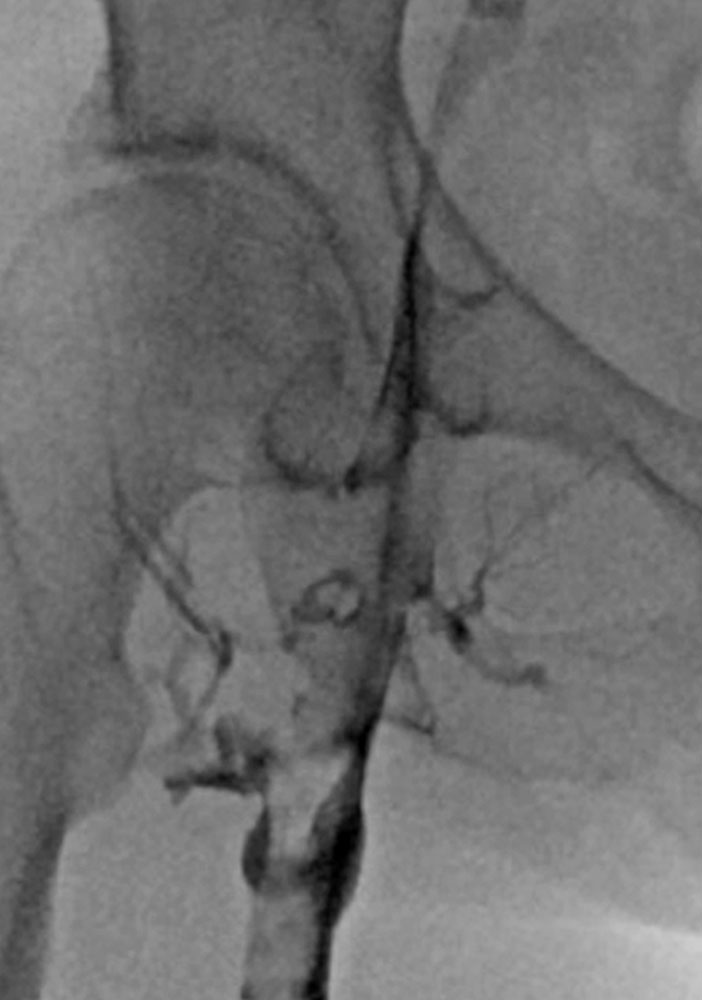

Phlebography has been almost entirely replaced by ultrasound, CT or MR phlebography for the diagnosis of phlebothrombosis and is no longer indicated. Phlebography nowadays is mostly performed as varicography in the direct puncture technique in the context of interventional procedures. In this situation the thrombus is visualized as an intraluminal contrast medium filling defect in the vein.

In the case of thrombosis of the central iliac veins, it may be difficult to detect thrombosis by transabdominal sonography because of overlaying structures such as bowel. Phlebography may also produce a false negative in this case. Cross-sectional computed tomography or magnetic resonance imaging may be helpful in such cases if a therapeutic consequence can be derived from it. A good alternative, especially in the area of the proximal common iliac veins, e.g., in May-Thurner syndrome, is intravascular ultrasound, which involves inserting a catheter with an integrated ultrasound probe directly into the vein.

Invasive measures today often include minimally invasive, catheter-guided mechanical or pharmacomechanical procedures. In these procedures, the acute thrombus is dissolved by mechanical or pharmacomechanical catheter therapy in a minimally invasive manner. Chronic occlusion, especially in the iliofemoral location descending from an iliac vein, can also be reopened minimally invasively, and stents are usually implanted. Open surgical therapy of acute thrombosis is very rarely indicated today, primarily in cases of iliofemoral thrombosis with occlusion of the pelvic venous circulation, and may be combined with creation of an arteriovenous fistula in the groin to keep the reopened vein open. However, appropriate measures should always be performed at a center.